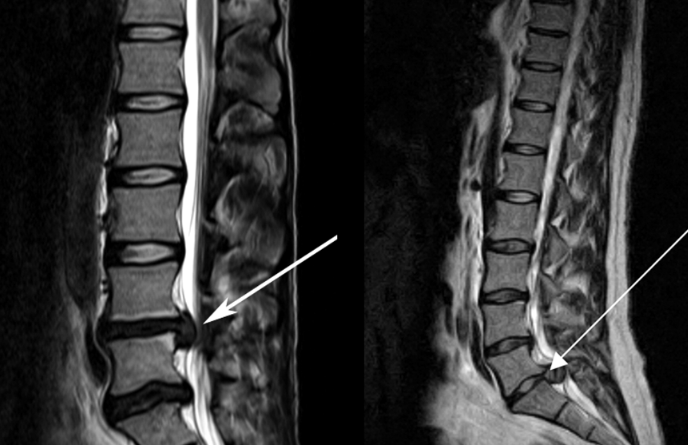

![]() 關(guān)于腰椎間盤突出 ![]() 腰椎間盤突出癥是纖維環(huán)破裂后髓核突出壓迫神經(jīng)根造成以腰腿痛為主要表現(xiàn)的疾病。腰椎間盤退行性改變或外傷所致纖維環(huán)破裂,髓核從破裂處脫出,壓迫腰椎神經(jīng),從而出現(xiàn)腰腿放射性疼痛。 ![]() 病因: 一、退行性變: 目前認(rèn)為,其基本病因是腰椎間盤的退行性變。退行性變是一切生物生、長、衰、亡的客觀規(guī)律,由于腰椎所承擔(dān)的特殊的生理功能,腰椎間盤的退行性變比 其他組織器官要早,而且進(jìn)展相對要快。這個過程是一個長期,復(fù)雜的過程。所謂腰椎間盤退行性改變:即由于椎間盤受體重的壓迫,加上腰部又經(jīng)常進(jìn)行彎曲、后伸等活動,易造成椎間盤的擠壓和磨損,尤其是下腰部的椎間盤,從而產(chǎn)生退行性改變。腰椎間盤退行性改變是本病發(fā)生的基礎(chǔ)?!?/p> 二、其他因素: 1、外力作用:在日常生活和工作中,部分人往往存在長期腰部用力不當(dāng)、過度用力姿勢或體位的不正確等情況。例如長期從事彎腰工作的煤礦工人和建筑工人需經(jīng)常彎腰提舉重物。這些長期反復(fù)的外力造成的損傷日積月累地作用于椎間盤,加重了退變的程度。 2、椎間盤自身解剖因素的弱點(diǎn): (1) 椎間盤在成人之后逐漸缺乏血液循環(huán),修復(fù)能力也較差,特別是在退變產(chǎn)生后,修復(fù)能力更加微弱。 (2) 椎間盤后外側(cè)的纖維環(huán)較為薄弱,而后縱韌帶在腰5、骶1平面時寬度顯著減少,對纖維環(huán)的加強(qiáng)作用明顯減弱。 (3) 腰骶段先天異常:腰骶段畸形可使發(fā)病率增高,這些異常造成椎間隙寬度不等,并常造成關(guān)節(jié)突出,關(guān)節(jié)受到更多的旋轉(zhuǎn)勞損,使纖維環(huán)受到的壓力不一,加速退變。 3、種族、遺傳因素:有色人種發(fā)病率較低,例如印第安人和非洲黑人等發(fā)病率較其他民族明顯要低。 ![]() 2 病理 腰椎間盤突出癥的病理變化過程大致可分為三個階段: 1、突出前期:髓核因退變和損傷可變成碎塊狀物,或呈瘢痕樣結(jié)締組織,變性的纖維環(huán)可因反復(fù)損傷而變薄變軟或產(chǎn)生裂隙。此期病人可有腰部不適或疼痛,但無放射性下肢痛。也有的人原無病變,可因一次大的暴力引起髓核突出。 2、突出期:外傷或正常的活動使椎間盤壓力增加時,髓核從纖維環(huán)薄弱處或破裂處突出。突出物刺激或壓迫神經(jīng)根即發(fā)生放射性下肢痛,或壓迫馬尾神經(jīng)發(fā)生大小便功能障礙。在老 年患者,可因椎間盤退變,整個纖維環(huán)變得軟弱松弛,椎間盤可呈彌漫性向周圍膨出。 3、突出晚期:腰椎間盤突出后,病程較長者,椎間盤本身和其他鄰近結(jié)構(gòu)均可發(fā)生各種繼發(fā)性病理改變。 3 誘發(fā)因素 腰椎間盤突出癥的基本因素是椎間盤退變,但某些誘發(fā)因素可致使椎間隙壓力增高,引起髓核突出。此種誘發(fā)因素常與以下因素有關(guān): 1. 年齡因素:腰椎間盤突出癥的好發(fā)年齡在30-50歲,平均手術(shù)年齡在40歲,因此退變可能是其重要因素。 2. 身高與性別:有人認(rèn)為身材過高也會易發(fā)腰突癥,而男性發(fā)病率是女性的5倍?!?/p> 3. 增加腹壓:臨床上有約1/3的病人在發(fā)病前有明確的增加腹壓的因素,如劇烈的咳嗽、噴嚏、屏氣、用力排便等。使腹壓增高,破壞了椎節(jié)與椎管之間的平衡狀態(tài)。 4. 不良體位:人在完成各種工作時,需要不斷更換各種體位以緩解腰部壓力,如長期處于某一體位不變,即可導(dǎo)致局部的累積性損傷。特別是長期處于不良姿勢更容易誘發(fā)本病。 5. 職業(yè)因素:重體力勞動者發(fā)病率最高,白領(lǐng)勞動者最低。汽車駕駛員由于長期處于顛簸和振動狀態(tài),椎間盤承受的壓力大且反復(fù)變化,也易誘發(fā)椎間盤突出。 6. 受寒受濕:寒冷或潮濕可引起小血管收縮、肌肉痙攣,使椎間盤的壓力增加,可能造成退變的椎間盤破裂。 ![]() ![]() ![]() ![]() 癥狀: 腰椎間盤突出癥患者最多見的癥狀為疼痛,可表現(xiàn)為腰背痛、坐骨神經(jīng)痛,典型的坐骨神經(jīng)痛表現(xiàn)為由臀部、大腿后側(cè)、小腿外側(cè)至跟部或足背的放射痛。據(jù)臨床統(tǒng)計,約95%的腰突癥患者有不同程度的腰痛,80%的患者有下肢痛。特別是腰痛,不僅是腰椎間盤突出最常見的癥狀,也是最早出現(xiàn)的癥狀之一。 ![]() ![]() ![]() 檢查: 1、X線:腰椎間盤所包括的髓核、纖維環(huán)和軟骨板密度均較低,在X線下并不顯影,因此臨床上腰突癥患者的腰椎X線平片可僅有一些非特異性的變化,甚至無異常變化。因此單純腰椎平片并不能作為有無腰椎間盤突出癥的直接依據(jù),但X線能發(fā)現(xiàn)腰椎的退行性改變和結(jié)構(gòu)異常,對提示椎間盤的退變有重要意義,并且能排除其他的一些腰椎疾患,如腰椎結(jié)核、腫瘤和腰椎滑脫等。典型的腰椎間盤突出癥患者通過病史、體征和X線平片即能作出初步的診斷?!?/p> 2、CT檢查:腰椎的CT可以清楚地顯示椎間盤突出的部位、大小、形態(tài)和神經(jīng)根、硬脊膜受壓的情況,同時還可顯示黃韌帶肥厚、小關(guān)節(jié)增生、椎管和側(cè)隱窩狹窄等情況。對腰椎間盤突出癥診斷的準(zhǔn)確率達(dá)到80%-92%。 3、核磁共振(MRI):核磁共振沒有輻射,可以多方位成像(橫斷面、冠狀面、矢狀面和斜面),對解剖細(xì)節(jié)顯示較好,對組織結(jié)構(gòu)的細(xì)微病理變化更敏感(如骨髓的浸潤),可以排除神經(jīng)和脊柱腫瘤等。對于一些落到椎管的髓核組織也不會遺漏?!?/p> 4、脊髓造影:脊髓造影利用椎管內(nèi)蛛網(wǎng)膜下腔的空隙,注入造影劑后在X線下攝片,顯示椎管內(nèi)部結(jié)構(gòu)。目前常用水溶性造影劑,能較清晰地顯示硬膜腔、馬尾神經(jīng)和神經(jīng)根鞘,對腰椎間盤突出癥的診斷可達(dá)90%左右,主要X線表現(xiàn)為硬膜囊壓迫征象和神經(jīng)根鞘壓迫征象。但由于CT和MRI在臨床的廣泛應(yīng)用,無創(chuàng)傷且診斷率更高,脊髓造影在臨床上的應(yīng)用已經(jīng)大大減少,而且由于它副作用較大,甚至可能造成截癱等嚴(yán)重情況,目前主張慎重選用。 5、肌電圖:肌電圖是對周圍神經(jīng)與肌肉的電生理檢查方法,可用于觀察并記錄肌肉在靜止、主動收縮和支配其的周圍神經(jīng)受刺激時的電活動,同時也可用來測量周圍神經(jīng)的傳導(dǎo)速度。在腰椎間盤突出癥上,肌電圖主要通過檢查雙下肢肌肉的興奮性來反映相應(yīng)神經(jīng)根的狀態(tài),并根據(jù)異常電活動的分布范圍來判斷椎間盤突出和神經(jīng)根受壓的節(jié)段。在脊神經(jīng)根和馬尾神經(jīng)受壓的病人,肌電圖陽性率可達(dá)80%-90%,但與CT和MRI相比并不是首選的檢查手段,可用于輔助診斷和判斷神經(jīng)根的受壓情況,同時也可以用來作為判斷治療后神經(jīng)根恢復(fù)情況的指標(biāo)之一。 ![]() ![]() ![]() 預(yù)防: 腰椎間盤突出癥是在退行性變基礎(chǔ)上積累傷所致,積累傷又會加重椎間盤的退變,因此預(yù)防的重點(diǎn)在于減少積累傷。 日常注意事項(xiàng): 1.平時要有良好的坐姿,睡眠時的床不宜太軟。 2.長期伏案工作者需要注意桌、椅高度,定期改變姿勢。 3.職業(yè)工作中需要常彎腰動作者,應(yīng)定時伸腰、挺胸活動,并使用寬的腰帶。 4.應(yīng)加強(qiáng)腰背肌訓(xùn)練,增加脊柱的內(nèi)在穩(wěn)定性,長期使用腰圍者,尤其需要注意腰背肌鍛煉,以防止失用性肌肉萎縮帶來不良后果。 5.如需彎腰取物,最好采用屈髖、屈膝下蹲方式,減少對腰椎間盤后方的壓力。 ![]() ![]() ![]() 治療: (一)中醫(yī)外敷療法: 腰椎間盤突出可以外貼 腰突正骨膏,其有效成分可透入皮膚產(chǎn)生活血,止痛,化淤,通經(jīng)走絡(luò),開竅透骨,祛風(fēng)散寒等效果,并通過藥物的歸經(jīng)作用而調(diào)理機(jī)體陰陽平衡,滲透于表皮,刺激神經(jīng)末梢,促進(jìn)局部血液微循環(huán),扶正固本、改善體質(zhì),從根本上、全方位針對腰椎疾病病機(jī)特點(diǎn)而發(fā)揮療效,改善病變周圍組織營養(yǎng),起到修復(fù)骨病組織的作用,最終達(dá)到治療目的。 (二)自我治療: 1.腹肌鍛煉: 也就是仰臥起坐。每次做十個,每天三次。(可根據(jù)患者的體質(zhì)來定,不可逞強(qiáng))。 2.交叉扭腰: 兩腳分開與肩寬,腳尖向內(nèi)兩臂伸直,一手在體側(cè),一 手舉過頭頂。如果右手在上,先向左側(cè)后方擺。左側(cè)相反。于此同時腰部也隨之扭動,左右各100次。 3.抱膝觸胸: 處于仰臥位,雙膝屈曲,手抱住膝部,使盡量靠近胸部,然后放下,一上一下為一個動作,可持續(xù)30個。 4.腰背肌鍛煉: 處于平臥,雙膝彎曲放在床上,然后用力將臀部抬起,離開床面10厘米。這時您會感覺到腰背部在用力,堅(jiān)持5秒鐘,反復(fù)10下。 ![]() (三)非手術(shù)治療: 非手術(shù)療法是治療腰椎間盤突出癥的基本療法,約80%以上的患者經(jīng)保守治療均可得到緩解和痊愈。其主要療法有: 1.日常家庭治療:早期腰椎間盤突出癥,癥狀輕微,不需要做特殊的治療。第一,注意臥床休息,避免腰椎受外力壓迫,第二,應(yīng)用其他方法積極鍛煉腰部肌肉力量。 2.牽引治療; 3.推拿按摩治療; 4.物理治療; 5.消炎鎮(zhèn)痛藥物; 6.減輕神經(jīng)根水腫藥物。 (四)推拿治療: 1.解除腰臀部肌肉痙攣 2.拉寬椎間隙,降低盤間壓力 3.增加椎間盤外壓力 4.調(diào)整后關(guān)節(jié),松解粘連 5.促使受損傷的神經(jīng)根恢復(fù)功能 (五)微創(chuàng)治療: 微創(chuàng)治療方法的目的是消除腰椎間盤突出的髓核以解除對神經(jīng)的壓迫。微創(chuàng)治療技術(shù)采用可視設(shè)備,創(chuàng)口不足一厘米有些甚至不足一毫米。消融或摘除髓核,從根本上解除致病因素,因而能夠取得很好的效果。 (六)手術(shù)治療: 腰椎間盤突出癥的手術(shù)原則是嚴(yán)格無菌操作,盡量保留不必去除的骨結(jié)構(gòu)和軟組織結(jié)構(gòu),以最小的創(chuàng)傷達(dá)到足夠的顯露,仔細(xì)徹底地去除病變組織,達(dá)到治療目的。 ![]() ![]() 綠柏相關(guān)產(chǎn)品: ![]() 懸吊訓(xùn)練療法是康復(fù)醫(yī)學(xué)中以持久改善肌肉骨骼疾病為目的的,應(yīng)用主動治療和訓(xùn)練的一個總的概念整合,是一種運(yùn)動感覺的綜合訓(xùn)練系統(tǒng),包括診斷與治療兩大系統(tǒng)。 產(chǎn)品特點(diǎn): 1.電腦軟件管理系統(tǒng),涵蓋患者信息管理、評估、訓(xùn)練、量表、報告、視頻教學(xué)六大模塊,輕松實(shí)現(xiàn)評估與訓(xùn)練一體化管理; 2.多點(diǎn)多軸設(shè)計,滿足不同治療方案設(shè)計; 3.懸吊工作站及各個懸吊點(diǎn),均能實(shí)現(xiàn)任意位置移動,一鍵解鎖,省時省力; 4.實(shí)時力反饋,精準(zhǔn)量化弱鏈測試及懸吊治療全過程,給治療師及患者最直觀的效果呈現(xiàn); 5.智能神經(jīng)肌肉促通裝置,可根據(jù)評估結(jié)果設(shè)置治療模式、頻率、時間等相關(guān)參數(shù),讓懸吊康復(fù)更加高效有針對性; 6.外觀高端大氣,結(jié)構(gòu)穩(wěn)固,給患者安全保障,增加治療信心。 ![]() |